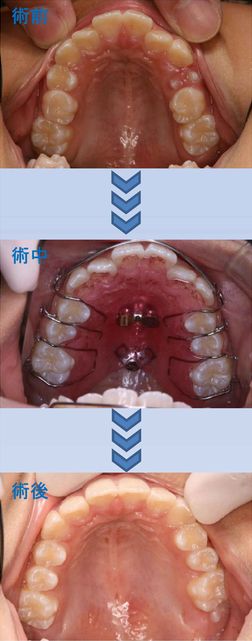

10歳8ヶ月の女の子。一番気になるところは、出っ歯。

固定式装置は友達がやっていて痛いといっていたから、取り外し式の装置で治して欲しいという希望がありました。

上顎に床矯正装置を装着し、歯の生え換わりを観察しながら装置を1度作り直して、出っ歯がきれに治りました。

痛みは全くありませんでした。

治療費:¥400,000(税別) 治療期間:1年4ヶ月

副作用・リスク:12歳臼歯が生えるときに歯並びが乱れることがある